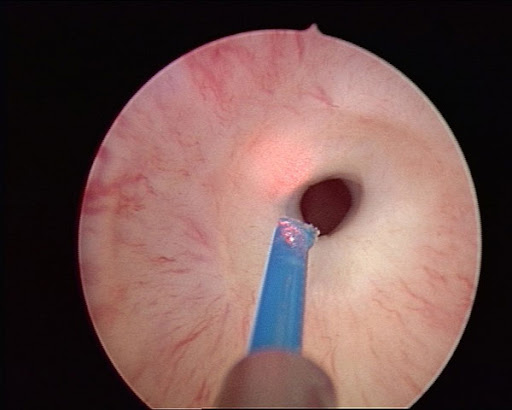

Lazer tedavisi, üretra darlığında kapalı (endoskopik) yöntemle uygulanan bir işlemdir. Bu teknikte, idrar kanalındaki dar segment özel bir cihaz yardımıyla görüntülenir ve lazer enerjisi kullanılarak dar alan kesilerek genişletilir. İşlem genellikle spinal veya genel anestezi altında yapılır.

En sık kullanılan lazer türü ürolojide Holmium:YAG lazer sistemidir. Ancak burada önemli olan nokta şudur: Lazer, üretra darlığında farklı bir ameliyat türü değil, klasik internal üretrotomi işleminin bir uygulama şeklidir. Yani amaç aynıdır; dar segmentin içeriden kesilerek açılmasıdır.